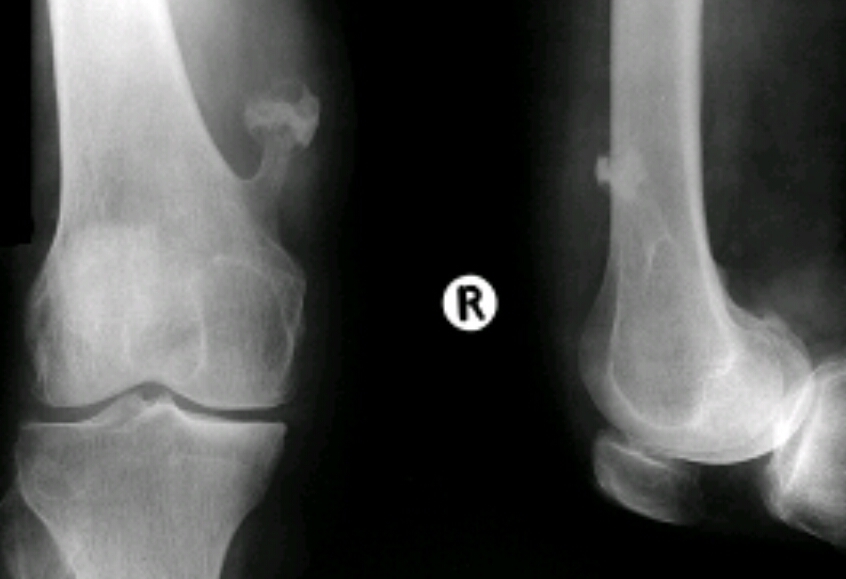

Findings? Diagnosis?

Multiple Osseous stalks of the tibia, fibula and femur

Hereditary multiple exostosis